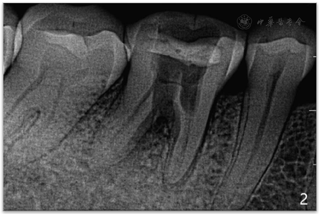

面呈开髓洞型,髓腔暴露,探及远中髓室底穿孔区(图1),面积约为4mm×3mm,穿髓孔区域探痛(+),叩(+),冷热刺激无反应,未探及牙周袋,患牙无松动。根尖片示:46

面可见低密度缺损影像,远中髓室底区域穿孔,大约4 mm×3mm,并伴有近中根管口的破坏,根尖区可见边界不清的低密度暗影(图2)。